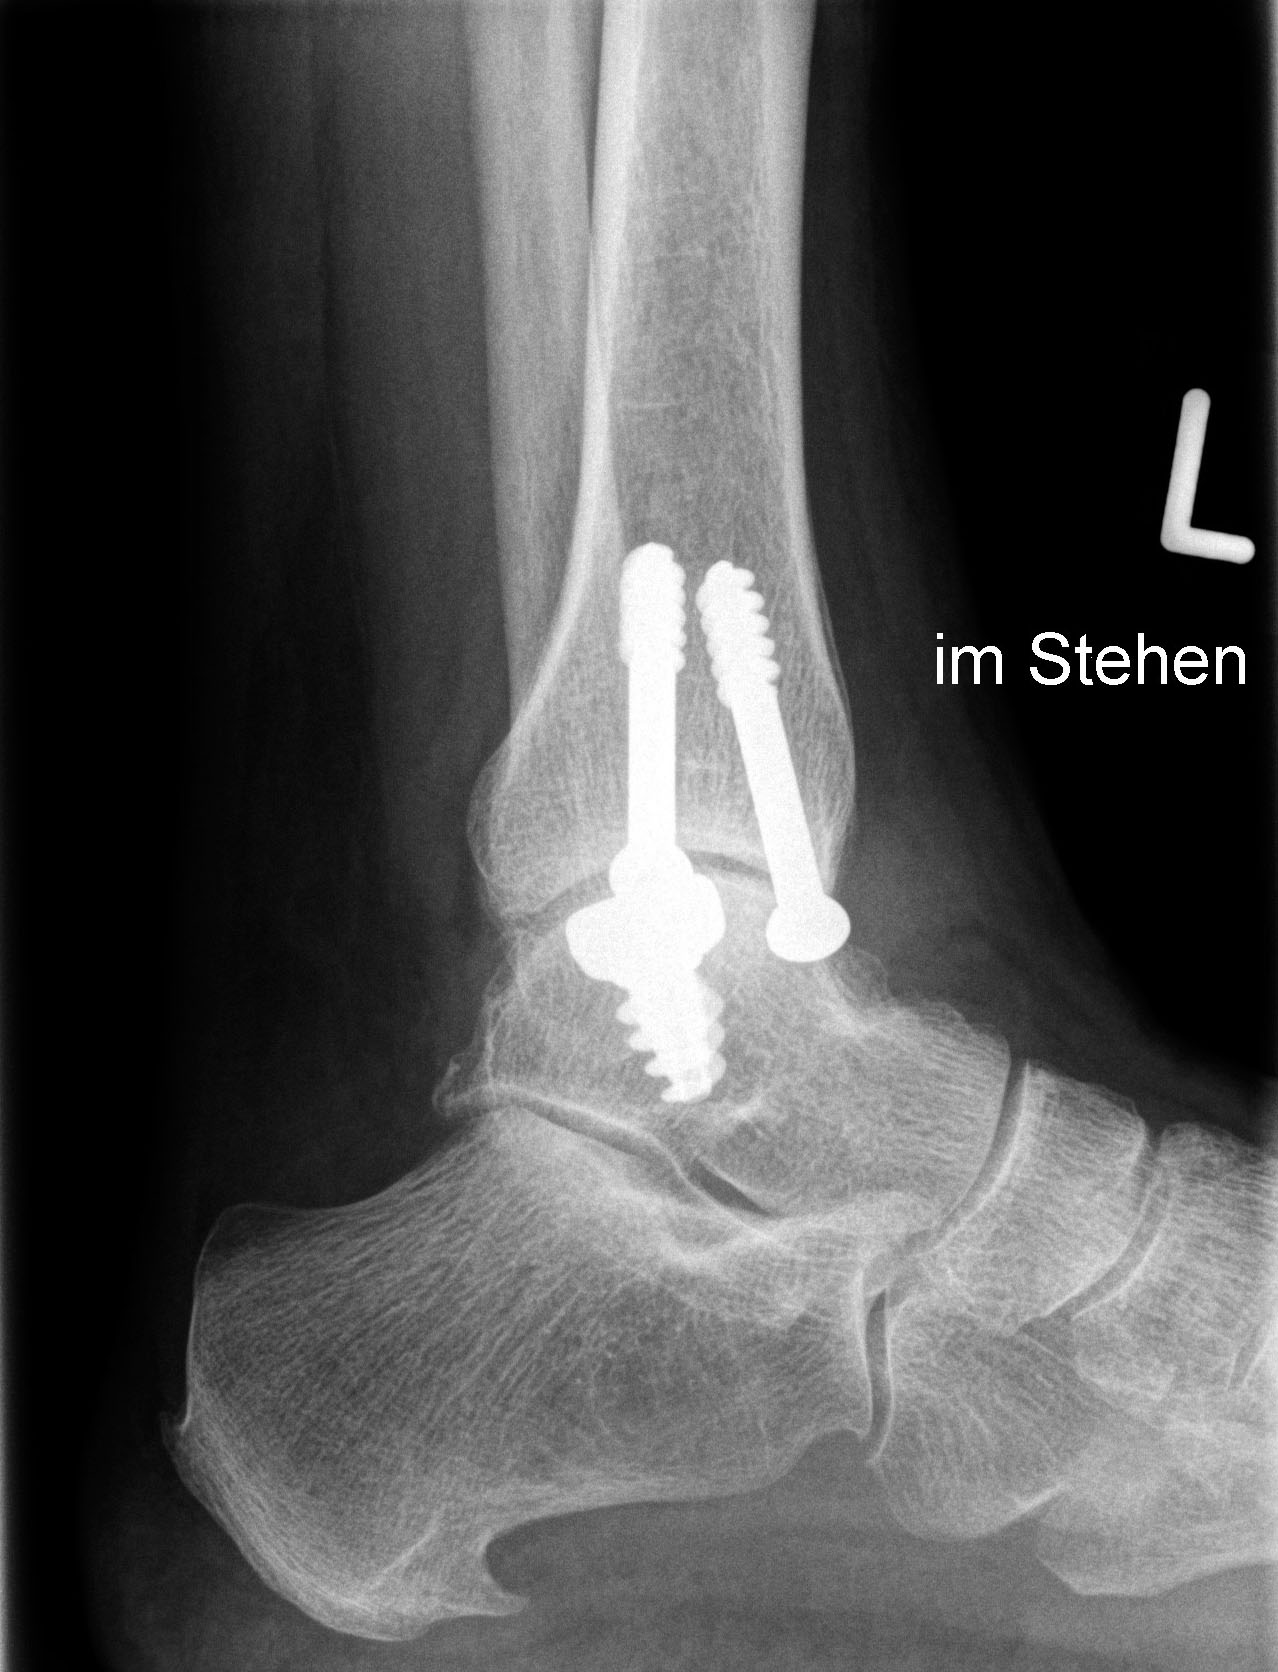

CAVE: Bei der postoperativen Röntgenkontrolle muss bedacht werden, dass die Knorpelschicht nicht abgebildet ist. Da das Implantat bei einer korrekten Positionierung unterhalb des Knorpelniveaus die knöcherne Fläche dennoch etwas überragt, kann dies zu einer Fehlinterpretation führen, dass das Implantat übersteht.

Zum Lesen der Bildbeschreibung und zur Vollansicht bitte die Bilder anklicken. Bilder: Sarah Ettinger.